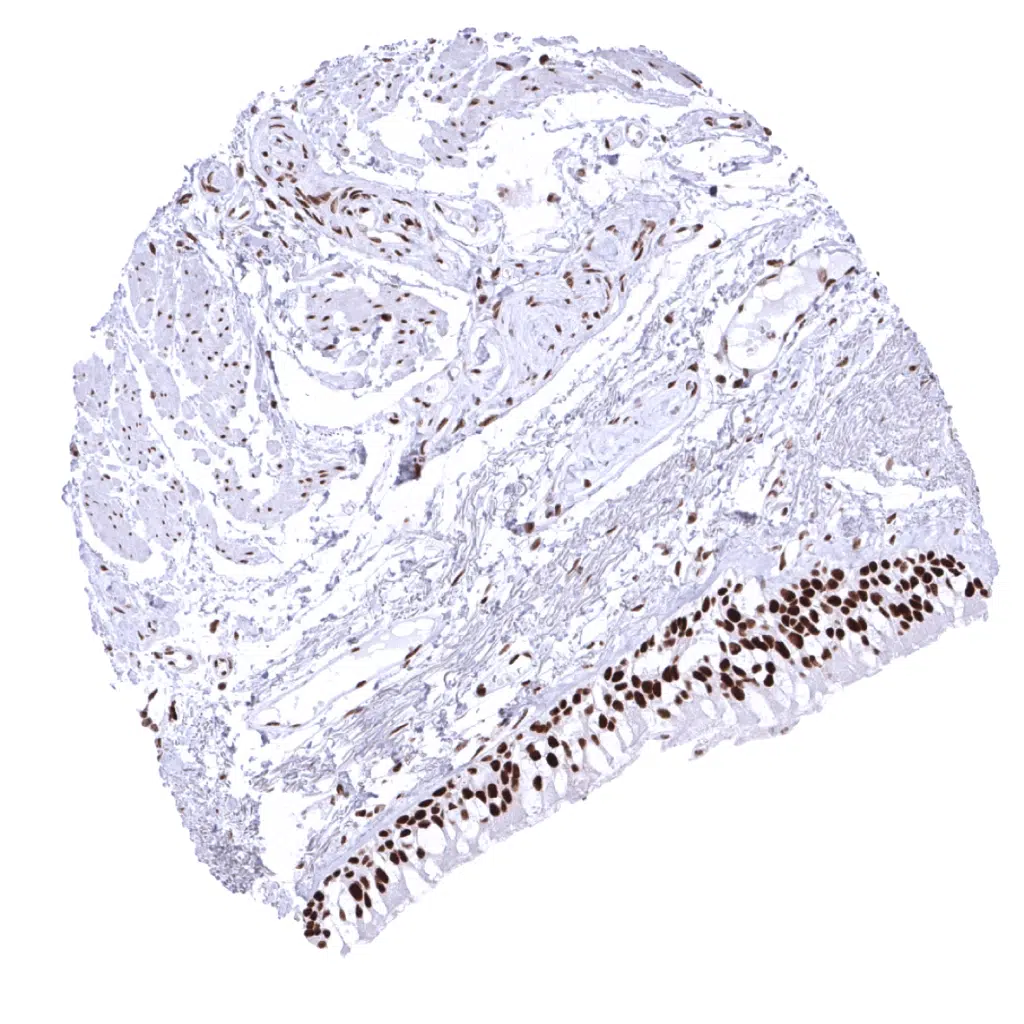

Colon descendens, muscular wall

Rectum, mucosa – In the colon (and rectum) epithelium, the MSH2 staining intensity decreases from the bottom to the top of the crypts.